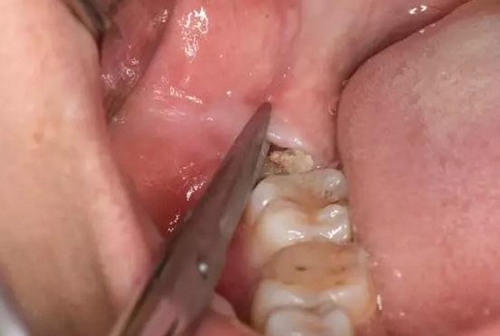

圖6. 剪刀做遠(yuǎn)中小切口、暴露遠(yuǎn)中邊緣嵴